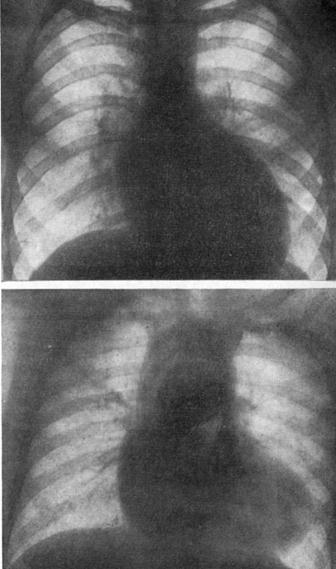

(клапанный стеноз легочной артерии, дефект межпредсердной перегородки и гипертрофия правого желудочка).

1 — левый желудочек; 2 — аорта; 3 — правый желудочек (гипертрофирован); 4 —правое предсердие (увеличено); 5 —левое предсердие (увеличено);

6 — сужение легочной артерии; 7 — дефект межпредсердной перегородки;

8 — легочный рисунок (обеднен).